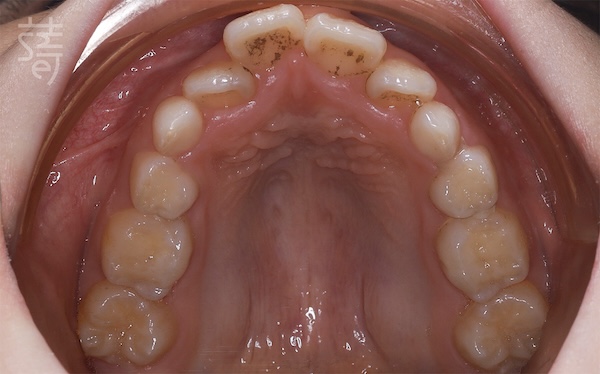

檢查後發現,小緹的牙弓偏窄、牙齒擁擠,門牙稍往前,加上她習慣用錯誤的方式呼吸,這些都會讓狀況逐漸惡化。

Dr. Ko found that Ti’s dental arch was narrow, her front teeth slightly protruded, and her breathing habits weren’t helping—issues that would likely worsen over time.

不過柯醫師也向媽媽解釋,這類狀況在齒列混合期孩子身上很常見,小緹正處在「第一階段矯正期」,也就是7~10 歲、乳牙和恆牙同時存在的階段。這時顎骨正快速發育,是早期介入的黃金時間,只要妥善接受治療,不僅能引導恆牙長在較理想的位置,也能降低未來需要大規模矯正的可能。

He explained that this is common in the mixed-dentition stage, when ages 7 to 10 offer a rare window: the jaw is still developing, and early orthodontic guidance can shape where adult teeth erupt and reduce the need for major treatment later on.

兩年後回診,X 光片上清楚顯示小緹的牙列變整齊了、牙弓更開展,嘴型也能自然閉合。那些早期努力的累積,就這樣安靜卻確實地發生在孩子身上。

Two years later, Ti returned for a follow-up, and the X-rays told the story clearly: a broader arch, straighter teeth, and a relaxed, natural lip seal. The quiet, steady work of early treatment had taken root.